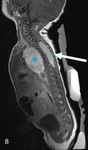

CT scan showing a thoracic paraspinal neuroblastoma wrapping around the spine

From the personal collection of Dr Jason Shohet